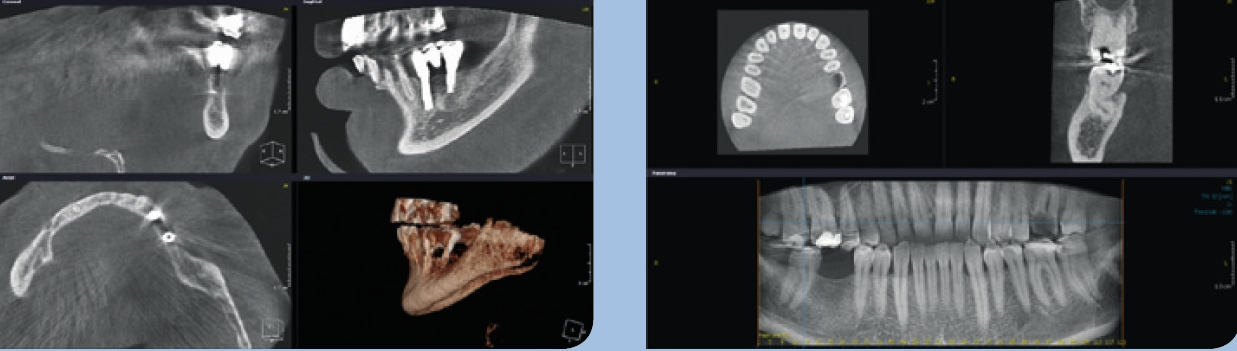

Bildbearbeitung/Software

Durch weitere Rechenprozesse können die Daten auf verschiedenste Weise dargestellt werden. Die multiplanaren Rekonstruktionen (MPR) stellen die sinnigste Weiterverarbeitung der Daten dar. Hierbei wird das Volumen durch senkrecht zueinander stehende Ebenen zerlegt, wodurch die Ansichten axial, sagittal und koronal erzeugt werden, ergänzt durch die oberflächengerenderte Ansicht (Abb. 9). Das Angebot entsprechender Bildbearbeitungsprogramme ist vielfältig, zumeist wird das DVT-Gerät mit einer adäquaten Software installiert und eingerichtet – ab diesem Zeitpunkt ist nun der/die Anwender/-in gefordert. In Deutschland ist die Absolvierung eines DVT-Kurses vor Inbetriebnahme eines DVT-Gerätes gesetzlich vorgeschrieben.